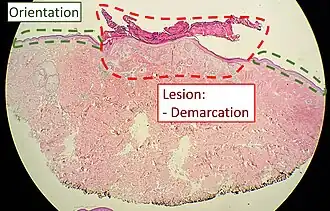

Orientation (lowest magnification): In this case oriented by the skin surface (green). A lesion is seen (red) and its demarcation can be discerned (diffuse in this case)

Orientation (lowest magnification): In this case oriented by the skin surface (green). A lesion is seen (red) and its demarcation can be discerned (diffuse in this case) -